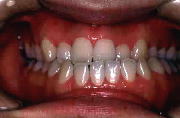

治療後の状態です。

乱杭いもなくなり、きれいな歯並びになりました。咬み合わせも良くなっています。